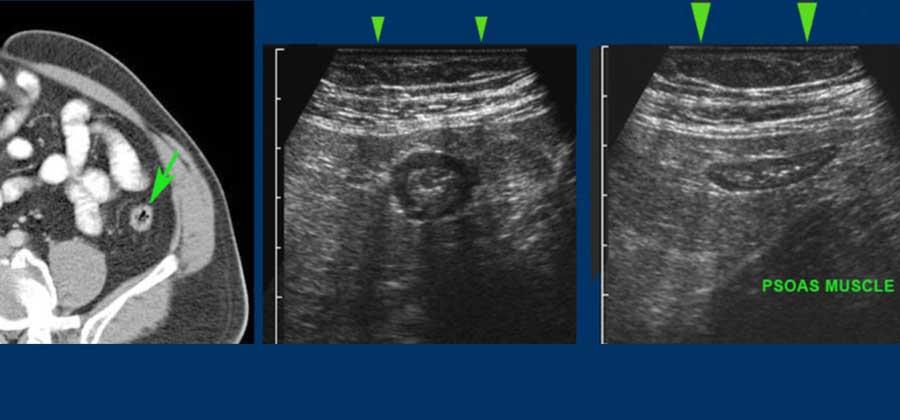

Hình ảnh CT cho thấy các mối tương quan giải phẫu trong ổ bụng thay đổi như thế nào khi ép có kiểm soát.

Trong quá trình ép, thành trước của ruột bị ép sát vào thành sau, loại bỏ tác động gây nhiễu của hơi và các thành phần khác trong lòng ruột.

Hình ảnh CT cắt dọc này cho thấy ruột thừa viêm nằm sau manh tràng (đầu mũi tên) với sỏi phân gây tắc nghẽn (mũi tên).

Bằng cách ép có kiểm soát bằng đầu dò siêu âm, manh tràng chứa hơi bị đẩy sang một bên và ruột thừa được hiển thị gần thành bụng (lưu ý thang đo cm).